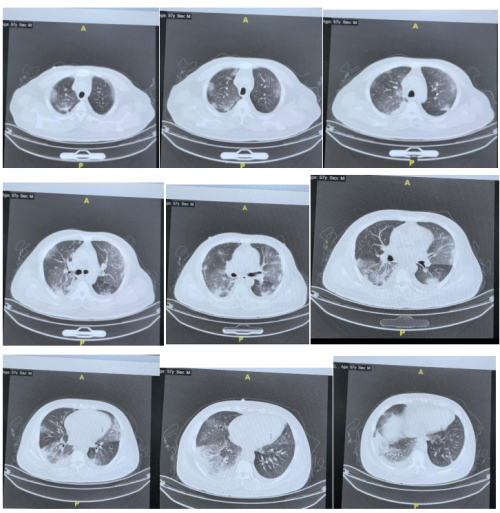

12月5日患者外送NGS血和痰的结果显示:新冠病毒阳性。同时调整抗生素为美罗培南联合莫西沙星。加用抗病毒口服药物先玛特伟。其他治疗未调整。治疗期间氧合指数逐渐好转,12月6-7日患者无创呼吸机高流量交替使用,呼吸支持条件下调,12月8日患者更换为鼻导管吸氧,可维持SPO2:95%。同时复查肺部CT:肺部病变明显好转。12月11日患者出院,转入血液科继续治疗骨髓瘤。

胸部CT变化:

12月8日: